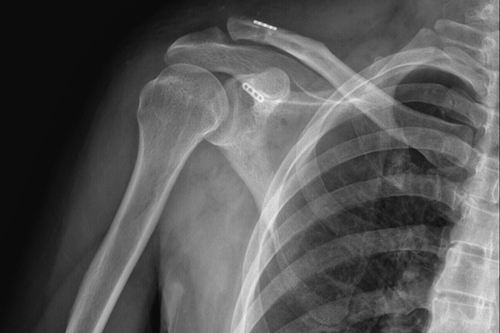

一名50岁的男性患者,因不慎摔伤致右肩关节肿痛,并伴活动受限4天后来附院求治。入院查体发现患者右肩部肿胀明显,右锁骨远端隆起畸形,局部明显按压出现疼痛,肩部外展活动受限,进行X线检查显示“右肩锁关节脱位”。骨三科医师团队根据患者病情,进行充分商讨,确定了手术治疗方案,决定为患者实施“右肩锁关脱位复位带袢钢板内固定术”。由副主任医师蒋宇平主刀,骨三科手术团队在患者锁骨上方及喙突处各取2cm手术切口,将肩锁关节复位后,使用瞄准器由喙突基底部向锁骨远端建立骨性隧道,最后将带袢钢板由骨道穿出后固定,术中出血仅10ml左右。

术后DR